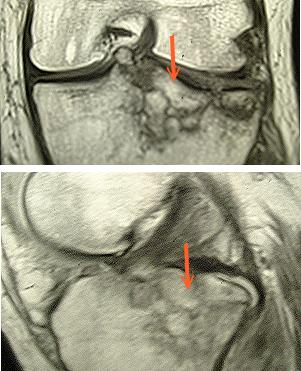

Bänderriß oder Meniskusquetschung, irgend so etwas hatte ich erwartet und mich darauf einstellt. Leider war dann das Ergebis niederschmetternd. Schienbeinkopf-Trümmerfraktur mit fibialem Ausriß des vorderen Kreuzbandes...Ja, das war's das für dieses Jahr. Ich glaube kaum, dass ich an einer Operation vorbeikomme, dann die üblichen Stationen: Krankenhaus, Bein stillgelegt, danach Reha...Dauer? Ungewiß! Vielleicht deshalb schon mal ein "Frohes Weihnachtsfest". Positiv zu vermelden: die Menisci sind intakt ;-). Soll man sich darüber freuen?